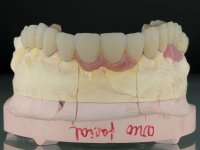

Alginate impressions were made at both arches arcades, accompanied by intermaxillary registration relations and collecting information with facial bow facial bow. In the laboratory, a provisional bridge with 13 elements in autopolymerizable acrylic was built, in which a metallic reinforcement was included. Teeth 1.7 / 1.4 / 1.3 / 2.2 / 2.3 / 2.4 and 2.6 were used as pillars. The metal-ceramic bridge was removed after performing longitudinal cuts with diamond burs. The dental abutments were reprepared and the temporary bridge was relined in the mouth with self-curing acrylic. After confection of the provisional bridge, a gingival epithesis was made using composite resin with gingival tonality in order to function as a mock-up, which allowed the patient to preview the possibility of using gingiva shade ceramics in the final work. This option was approved by the patient. Subsequently, the placement of two implants in the first quadrant was planned and executed. The provisional monoblock was removed for placement of the implants, and after surgery was again cemented provisionally. After the osseointegration period, the impressions were made to the maxilla. In the anterior zone, impregnated gingival retraction cords were used, and in the posterior areas, kaolin paste was used. Implant printing utilized the open tray technique. The printing material used was soft and regular putty addition silicone, both fast-setting. In the laboratory, the model of provisional restorations and the gingiva epithesis mock-up served as orientation for waxing the infrastructure. The plaster work model and the waxing of the infrastructure were placed in a laboratory scanner and yielded a digital work model, in which the scanning of the waxed infrastructure was superimposed. This overlay facilitated the CAD design of the Zr infrastructure. Subsequently, the CAD drawing for a CAM milling process provided the Zr pieces. The infrastructure was pigmented with a pinkish coloration, which favors the subsequent placement of gum shade ceramic. During the modeling of the infrastructure, the need to increase the occlusal wear on tooth 1.4 was detected. This was done in the real working model cast and an acrylic wear control guide was created, which accompanied the proof of the infrastructures. Corrective wear and Zr parts test were performed in mouth. During the test, the color choice of the gum shade ceramic was reassessed. The treatment was finished in the laboratory, and after approval by the patient, was definitively placed in the mouth.